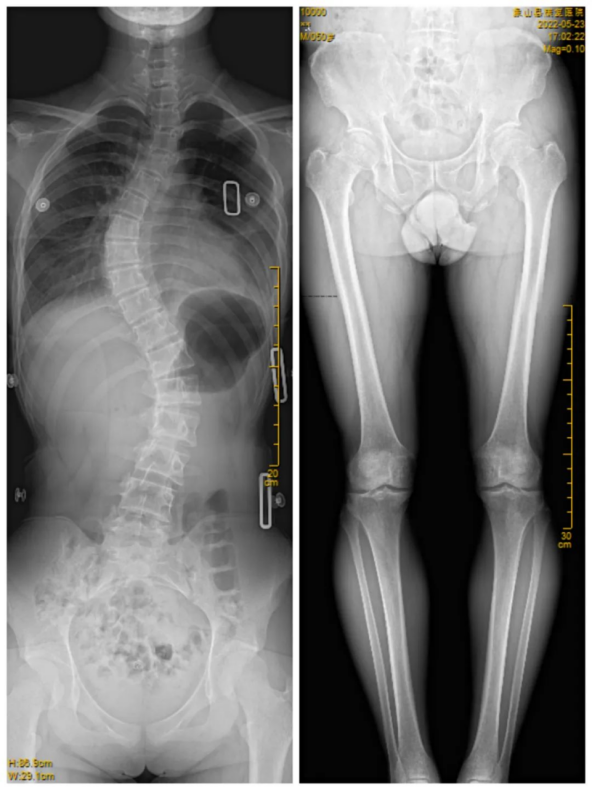

臨床在診治脊柱及下肢畸形時(shí),一些病情嚴(yán)重的患者往往需要手術(shù)矯正治療,這就需要對(duì)其進(jìn)行手術(shù)前后拍攝全脊柱或全下肢的X光片作為依據(jù),以便分析病情、制定手術(shù)方案和評(píng)估術(shù)后療效。目前廣大青少年及學(xué)生由于學(xué)業(yè)負(fù)擔(dān)重,時(shí)常接觸電子產(chǎn)品,更加容易出現(xiàn)脊柱側(cè)彎畸形等病變,脊柱全長(zhǎng)的攝片能及早地發(fā)現(xiàn)脊柱側(cè)彎及側(cè)彎的程度,及早地進(jìn)行臨床干預(yù)及治療。

常規(guī)DR攝片機(jī)拍攝面積有限,最大規(guī)格僅有43cm,但成人男性全脊柱長(zhǎng)度平均為70-75cm,女性為66-70cm,而全下肢更長(zhǎng)。常規(guī)攝片技術(shù)不能一次性拍攝出完整的全脊柱或全下肢的X光影像。例如在沒(méi)有拼接技術(shù)以前,全脊柱的拍攝需要分別拍攝頸椎、胸椎、腰椎的X光片,雖然能夠觀察到局部的側(cè)彎情況,但不能觀察到三者之間的連續(xù)性,這就增加了這類(lèi)疾病的診治難度。

而這醫(yī)用數(shù)字X射線攝影系統(tǒng),具有影像自動(dòng)拼接功能,一次最多可實(shí)現(xiàn)4張影像的拼接任務(wù),拍攝長(zhǎng)度可達(dá)145cm,使全脊柱及全下肢能夠得到完整清晰的成像。拼接圖像后處理技術(shù),可以為醫(yī)生提供高精準(zhǔn)度的臨床數(shù)據(jù),對(duì)于脊柱側(cè)彎的診斷治療的制定有著重要的參考價(jià)值。雙下肢負(fù)重位全長(zhǎng)拼接攝影能夠觀察雙下肢、髖關(guān)節(jié)及膝關(guān)節(jié)的病變程度范圍及整體形態(tài),對(duì)于髖、膝關(guān)節(jié)矯形手術(shù)及人工關(guān)節(jié)置換術(shù)等都有著非常重要的指導(dǎo)意義,為臨床治療提供重要參考依據(jù)。全脊柱及下肢全長(zhǎng)拼接攝影技術(shù)的成功開(kāi)展,能使患者得到科學(xué)的診斷及治療,為百姓提供更優(yōu)質(zhì)的服務(wù)。